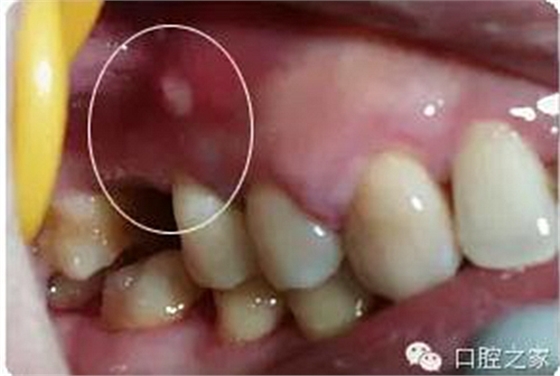

(3)根管壁側(cè)穿 手用擴(kuò)大針作根管清理或擴(kuò)大,較少出現(xiàn)側(cè)穿現(xiàn)象,除非是用大號(hào)擴(kuò)大針作強(qiáng)行擴(kuò)大。采用機(jī)用擴(kuò)大針或樁冠修復(fù)時(shí)進(jìn)行釘?shù)乐苽?,如操作不慎較易側(cè)穿。側(cè)穿后如未發(fā)現(xiàn)或處置不當(dāng),日后可出現(xiàn)有竇道的慢性根尖周炎。